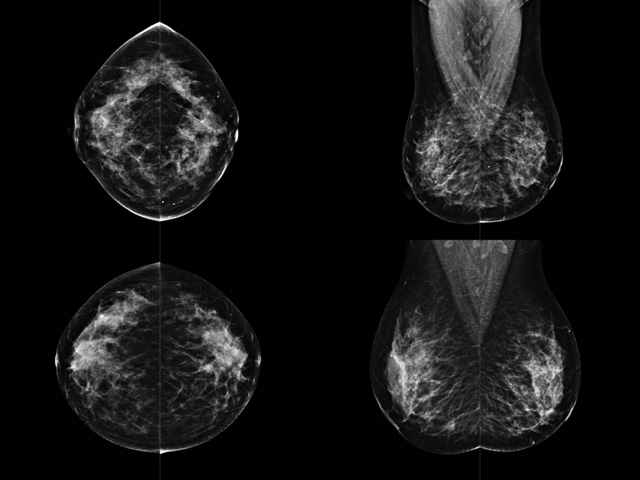

乳腺DR檢查的作用跟有什么細(xì)節(jié)需要注意事項

乳房檢查時候要注意一些細(xì)節(jié),需要更深入的了解這樣才能使檢查更準(zhǔn)確。乳腺DR是乳腺癌的篩查診斷工具設(shè)備。是乳房方面檢查的重要影像方法。它可以臨床檢查出早期的乳腺癌??梢耘袛嗔夹詯盒?。因為它可以檢查出早期的病變。對良性惡性檢查的準(zhǔn)確率達(dá)到90%以上。發(fā)病高峰年齡為45歲到54歲。50歲檢查出來乳腺癌病患,可以讓死亡率下降3成。所以30-40歲女性每年做一次乳腺DR檢查。40歲以上就一年兩次。如果家族史有乳腺癌的30歲以下也需要做檢查。清晰顯示乳腺各層組織嚴(yán)重的乳腺增生,乳腺炎,乳腺外傷也建議1年檢查一次。極大提高了早期乳腺癌的敏感度和診斷率。

大角度、高質(zhì)量的乳腺檢查,可以讓女性帶來身體健康安全。為醫(yī)生提供了高清影像數(shù)據(jù)。乳腺檢查時候各個部位影像顯示出來。白色乳腺導(dǎo)管跟纖維結(jié)締組織。模糊的是脂肪。病變一般是不透明的白色。有需要放大來檢查。乳腺DR沒有重疊偽影。輻射劑量更少。因為乳腺癌發(fā)病每年都有所提高,對女性都造成了嚴(yán)重的身體健康危害。早做檢查早治療是不可忽視的舉措??梢源蟠蟮慕档?/span>死亡率。保證身體健康。一般檢查避開經(jīng)期,來完7天左右是最佳的檢查時間。絕經(jīng)的女性就沒有要求。孕婦不參加乳腺DR檢查, 6個月內(nèi)準(zhǔn)備妊娠的婦女也不宜行此檢查。